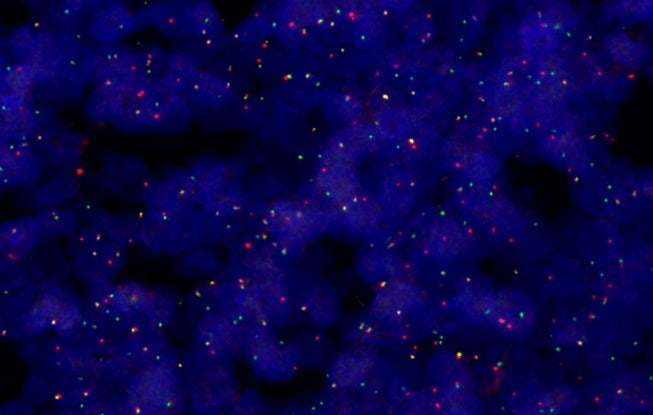

Voyez davantage de détails dans vos échantillons grâce à cinq modes d’imagerie – fond clair, lumière polarisée, fluorescence, fond noir et contraste de phase – et à la possibilité de combiner plusieurs techniques en une seule numérisation. Cette flexibilité ouvre la porte à de multiples possibilités pour l’observation d’échantillons d’histologie et de cytologie, allant de l’anatomopathologie de routine à la caractérisation moléculaire avancée de tissus cancéreux.

Il s’agit du scanner dont vous avez besoin aujourd’hui, mais doté de la flexibilité nécessaire pour évoluer avec les priorités de votre laboratoire. Que vous ayez besoin d’observer de la fluorescence multiplexée pour la découverte de marqueurs du cancer, d’utiliser la lumière polarisée pour étudier les amyloïdes dans les tissus cérébraux, ou d’analyser des échantillons grand format à la recherche de caractéristiques histologiques, le scanner SLIDEVIEW VS200 s’adapte à vos besoins pour relever chaque défi.